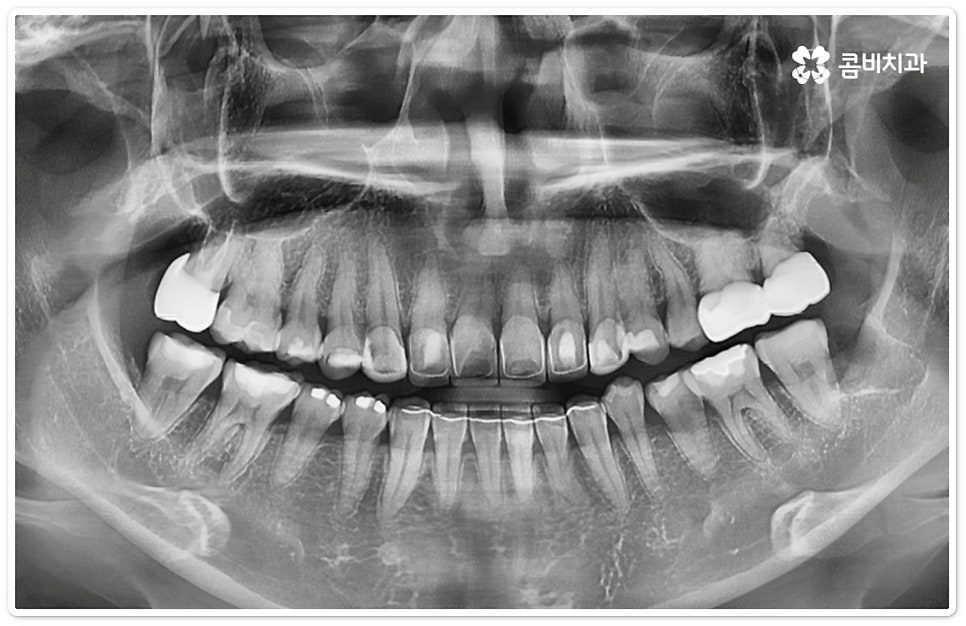

매복 형태의 사랑니는 잇몸을 절개하고 발치해야 하며, 특히 깊숙하게 누운사랑니발치 시에는 신경을 건드리지 않도록 사랑니를 조각내어 조심해서 빼내야 할 뿐 아니라 환자분들의 상태에 따라 잇몸뼈를 조금씩 삭제해야 할 수도 있기 때문에 이러한 고난도 시술에는 주변 조직의 손상을 최소화하고 혹시 모를 부작용의 위험을 줄이며 출혈 및 통증이 커지지 않도록 하기 위해서 시술자의 높은 숙련도가 더욱 요구된다고 할 수 있어요. 또한 매복된 사랑니의 각도, 뿌리 형태, 인접 치아와의 관계, 신경 위치 등을 정확하게 파악하고 체계적인 맞춤 계획을 세워 무리하지 않게 사랑니 발치 수술을 진행하기 위해서 정밀 진단이 가능한 3D CT 장비가 있는 치과에서 꼼꼼한 검사부터 받아보는 것이 중요할 거예요.

대부분의 환자분들이 치과에 대해 가지고 있는 두려움 중 많은 부분이 치아를 뽑아야 하는 상황과 관련되어 있는데요. 특히 누운사랑니발치 의 경우 말씀드린 것처럼 발치 전후로 해당 부위가 많이 부어오르고 피가 나며 통증과 멍 등을 동반하기도 하기 때문에 더욱 불안하게 생각하시고 치과 내원을 미루시는 분들도 있는데 안전하고 충분한 마취, 꼼꼼한 검진 및 각각의 케이스에 맞는 신중한 발치, 그리고 발치후 철저한 관리 및 환자분 입장에서의 주의사항 준수 등이 이행된다면 별다른 문제없이 시행할 수 있으니 너무 걱정하지 마시고 3D CT 등 정밀 검진 장비를 갖추고 처음부터 끝까지 면밀하게 케어해 주는 치과에서 숙련된 의료진과 함께 하시길 권유드리고 있어요.